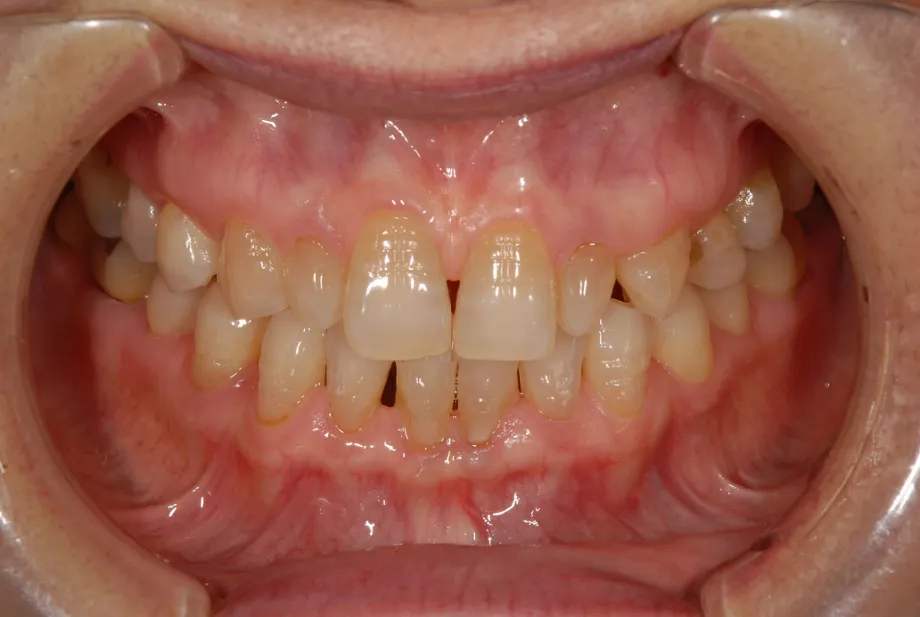

CASE1 60代女性 ダイレクトボンディングによる修復治療

初診

歯石除去で来院されました。

除去後、話を聞くと上顎の前歯の歯と歯の間が離れていることが

以前より気になっていると仰られ、治療計画を立案。

口腔内写真の撮影

残っている歯の問題点などを解析

顔全体・口元の写真を解析

前方・口元

側方・口元

さまざまな方向性から、歯のバランスや問題点を解析。

治療計画の立案を行います。